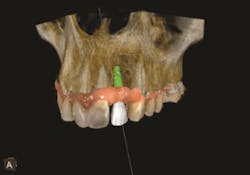

3. Then, using interactive software for treatment support, the data from the CBCT scan and digital impression are merged together. Figures 1-3.

What is the point of obtaining both extraoral and intraoral images? While the clinician can gain valuable insight about the mandible or maxilla, CBCT does not provide enough information about the surface detail of the teeth or soft tissues.2 When CBCT information is combined with the digital impression in the interactive treatment software, the doctor’s diagnostic capabilities are greatly enhanced, and, consequently, so is treatment planning.

The interactive implant planning software provides multiple views, enabling the clinician to evaluate potential implant receptor sites with greater accuracy. Through the software, bone can be “removed” or displayed with transparency, which helps in determining the precise placement of implants, abutments and translucent virtual teeth in proximity to the natural tooth root structure. A virtual crown is used to guide the placement of the virtual implant for optimal aesthetics and function. This allows for well-informed conclusions to be drawn about crown-to-implant ratio; implant diameter and length; and the design of the restoration in terms of screw or cement retention.3 Figures 4-5.